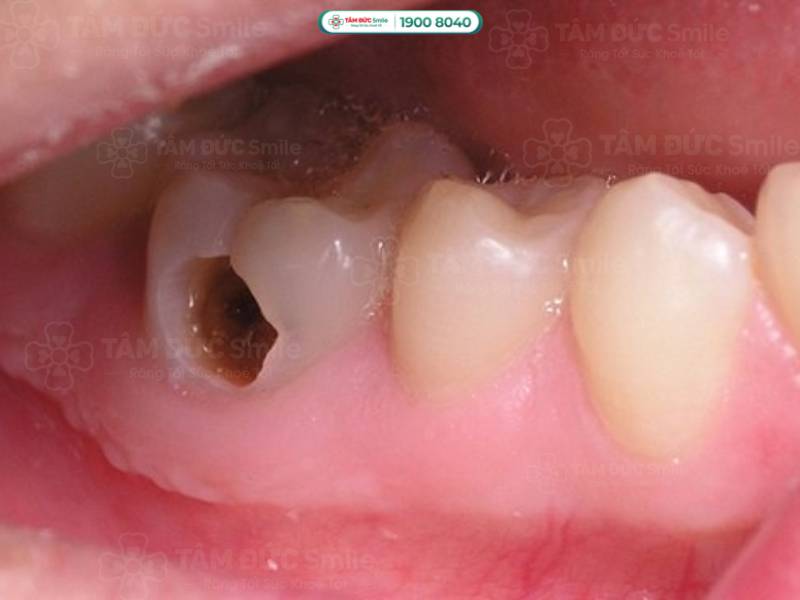

Dấu hiệu sâu răng độ 3 sẽ giúp bạn giải đáp thắc mắc răng sâu là gì. Tại thời điểm này, răng bị sâu xuất hiện các lỗ đen lớn, lộ ngà răng. Nếu không điều trị kịp thời, vi khuẩn sẽ phá huỷ đến lớp cuối cùng của răng là tuỷ răng.

Dấu hiệu sâu răng độ 3 sẽ xuất hiện các lỗ đen lớn, lộ ngà răng